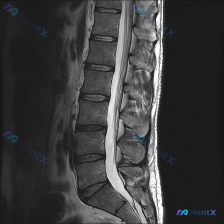

整理到一份腰椎影像资料,有点意思,拿出来和大家讨论。 资料是腰椎矢状位T2加权像,先说说能看到的表现: 1. 多节段椎间盘信号明显减低(黑盘征),L3/4、L4/5、L5/S1椎间隙还有不同程度塌陷; 2. L3/4、L4/5、L5/S1都有椎间盘突出,硬膜囊受压,L4/5、L5/S1看起来受压更明...